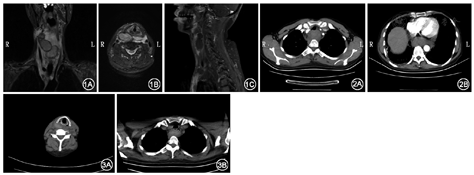

患者男,55岁,主因咽痛5 h于2015年12月24日入院。患者入院前5 h饮一口热水(约70 ℃)后开始出现右侧咽痛,当时无呛咳,继而出现进食障碍、咽部肿胀感,就诊于我科。体格检查见右颈部肿胀压痛,皮温无升高,会厌正常,右侧咽侧壁充血肿胀,声门未暴露,拟"右侧咽旁间隙感染"收治,予抗感染、激素处理后咽痛好转,查体见右侧咽侧壁充血肿胀好转,局部紫色血泡形成,颈部肿胀无明显变化。血常规示中性粒细胞比值升高(95.3%),余未见明显异常。颈部增强MRI考虑咽周感染,多发脓肿可能,甲状腺未见明显异常信号(图1)。入院后40 h,患者自觉精神紧张、剧烈胸痛,急查胸部CT示右侧颈部、咽后部及纵隔广泛病变,血肿可能(图2)。遂予手术探查。术中发现右颈动脉三角血肿形成,未见明显脓肿,予行气管切开术。术后予以抗感染、止血、鼻饲、局部加压包扎处理。术后行双侧颈动脉造影术示两侧颈内、外动脉、上颌动脉显示良好。患者术后1周复查颈胸部CT示血肿较前吸收(图3),予拔管出院。现跟踪随访1年,恢复良好。